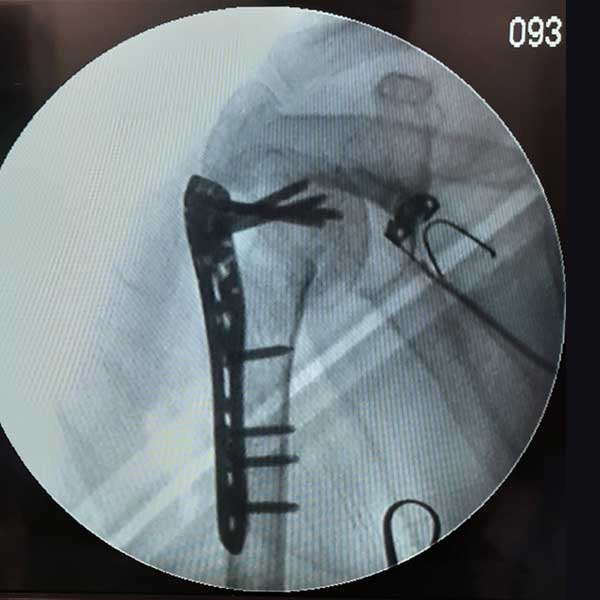

Case:7 Fracture Neck Femur with Implant failure and Re-Fixation with hemi-arthroplasty

Alcoholic Gardener by profession had slipped in bathroom & fell. He sustained fracture neck femur.He was operated with closed reduction & CC Screw fixation under IITV. Two weeks’ post fixation he again fell & sustained fracture in sub trochanteric region. He was treated with Hem-Arthroplasty with Tension band wiring.

Pre-Op

Post-Op

Post Fall

Oblique-Post Fall

Lat-Post Fall

Lateral-Post Prosthesis Fall

Post Prosthesis Fall

Post Uninon-3Months